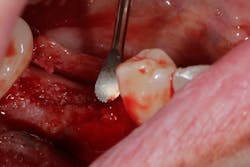

Related video: Extraction and socket grafting in preparation for dental implant placement

This surgical video demonstrates removal of a tooth with loss of buccal plate and grafting of the remaining socket with Geistlich Bio-Oss Collagen and Geistlich Bio-Gide to preserve the ridge for implant placement.